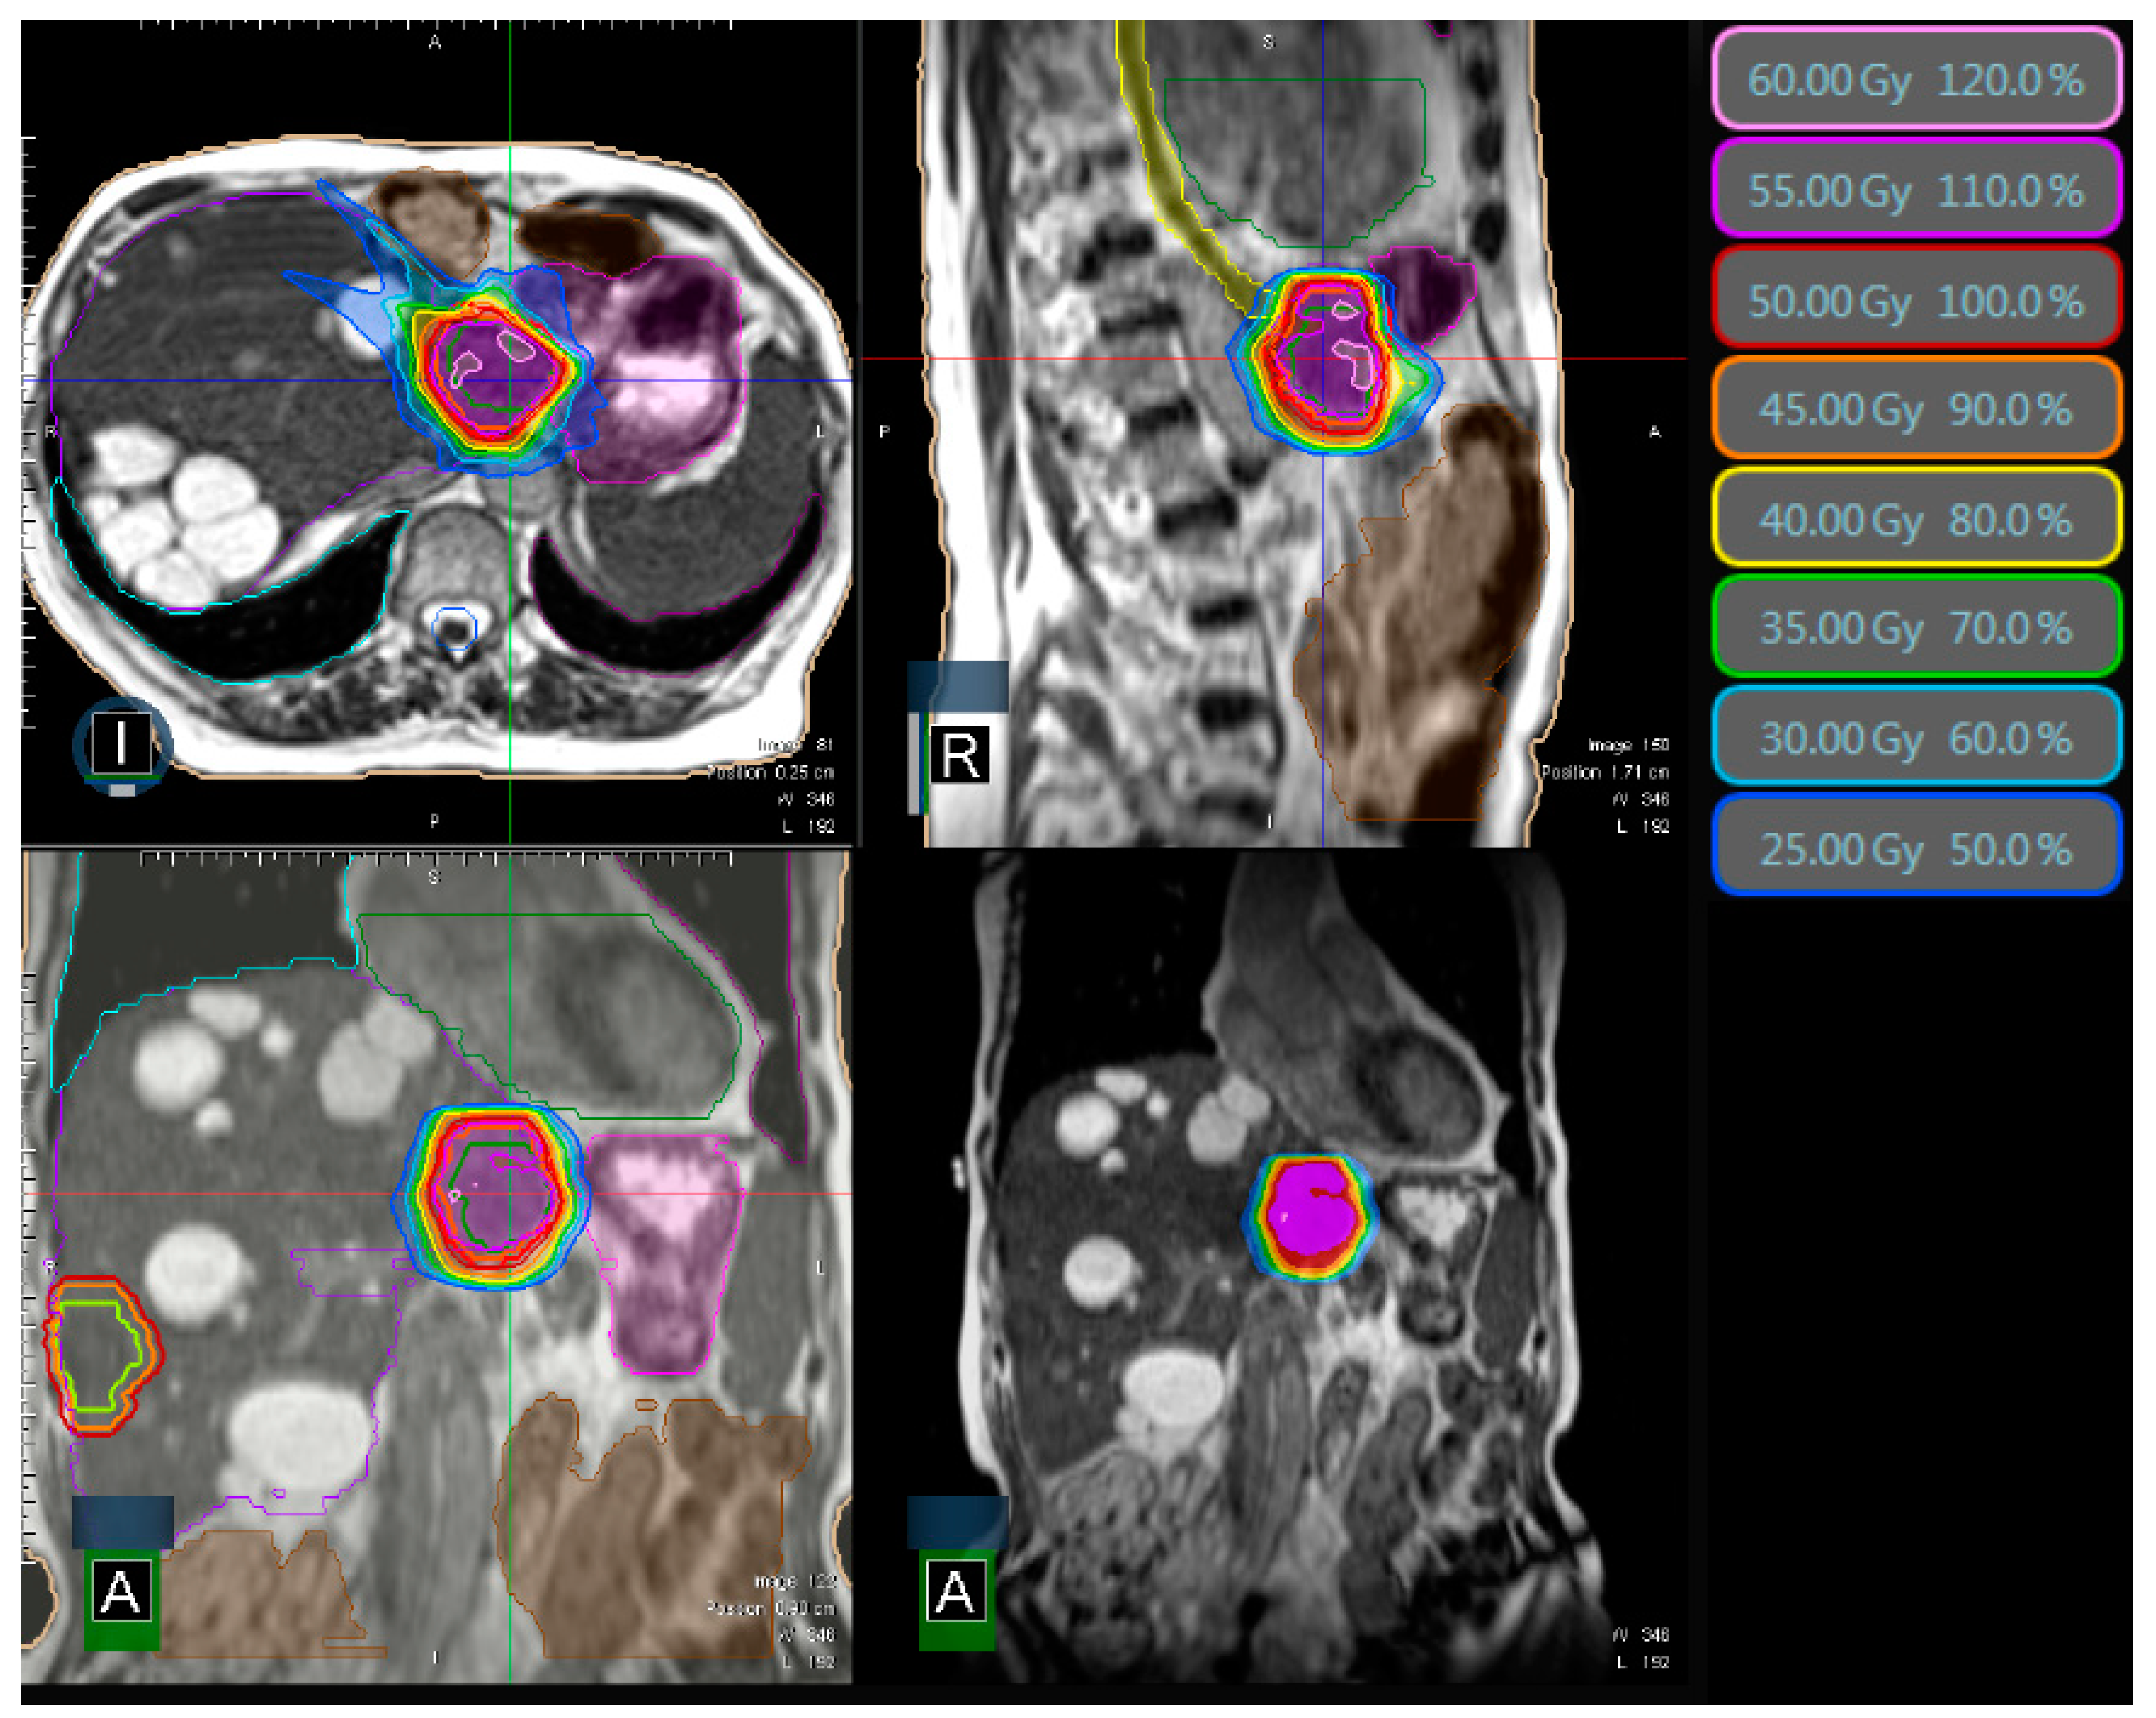

| median PTV volume | 54 cc (10–445 cc) |

| median prescribed total dose | 50 Gy (45–60 Gy) |

| median number of fractions | 5 (3–12) |

| median EQD2 (α/β = 10) | 83 Gy (54–94 Gy) |

| median BED (α/β = 10) | 100 Gy (65–113 Gy) |